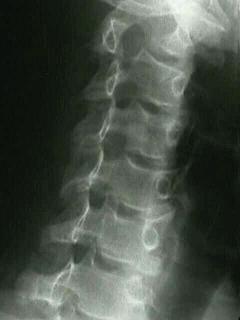

FIGURE 1-5 Left lateral radiograph of the lumbar spine. In lateral views the side indicator (LT) indicates the patient’s side closest to the x-ray detector.